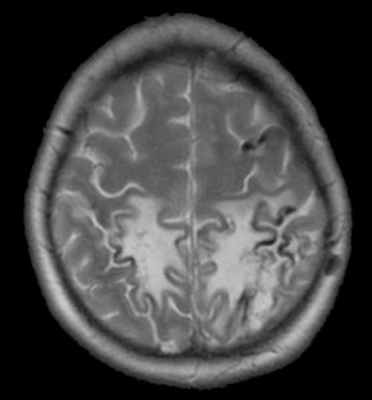

МРТ головного мозга. Т2-зависимая МРТ. Двухсторонний венозный инфаркт.